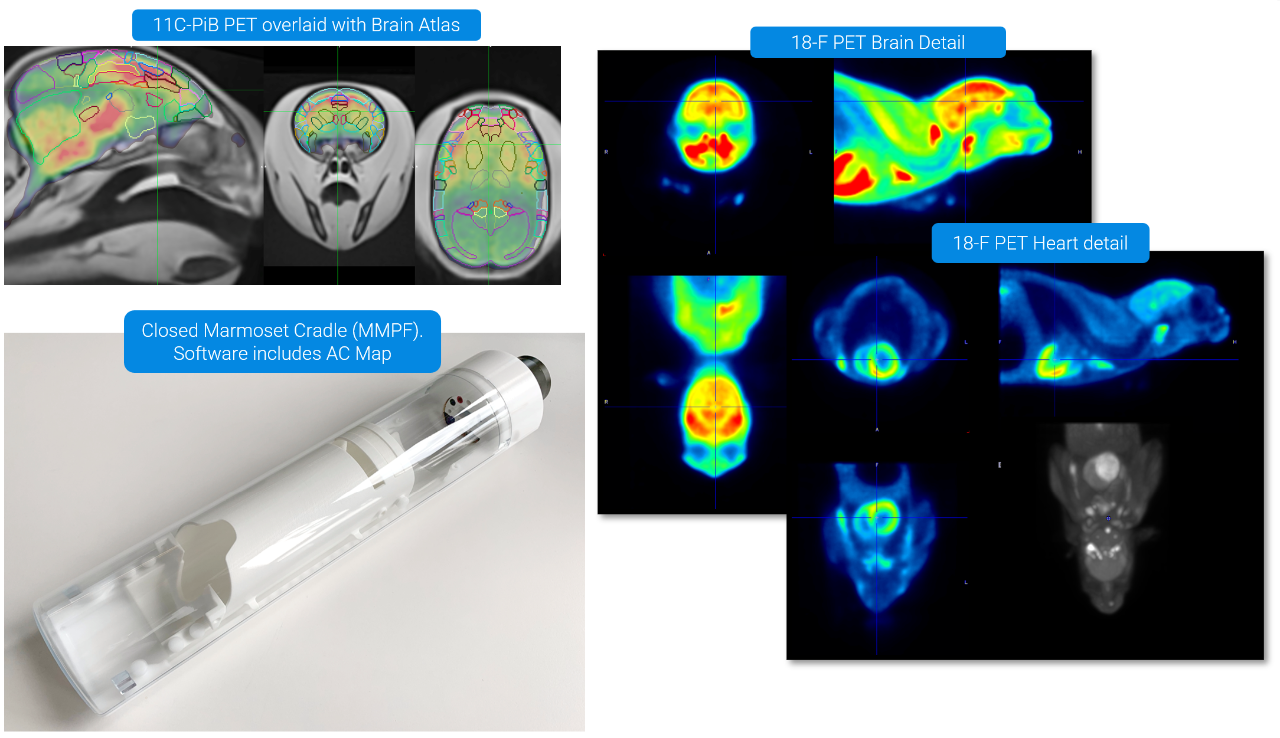

AD Model in Marmosets: Awake Imaging with 11C-PiB and 18F-FDG PET

PET/CT Si78